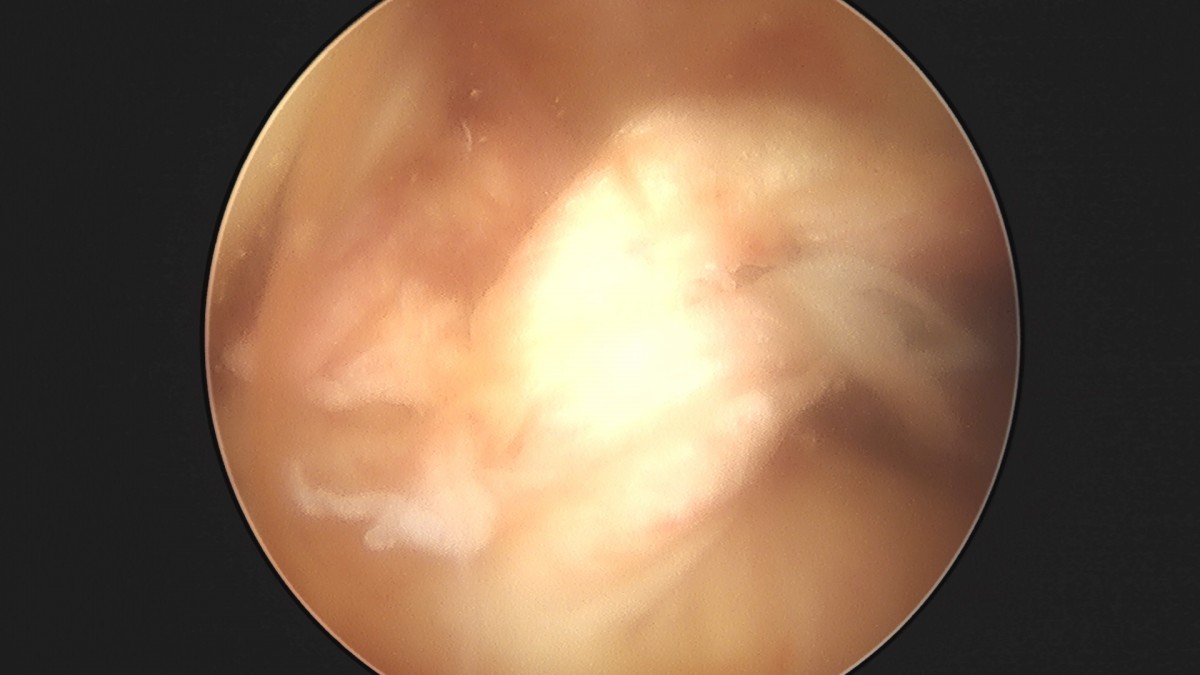

이재상원장님 전방십자인대 재건술 및 반월상 연골판 봉합술 윤두O 환자

dae765e4d9ac96aee867c9d6292d8784_1758007346_6867.jpg